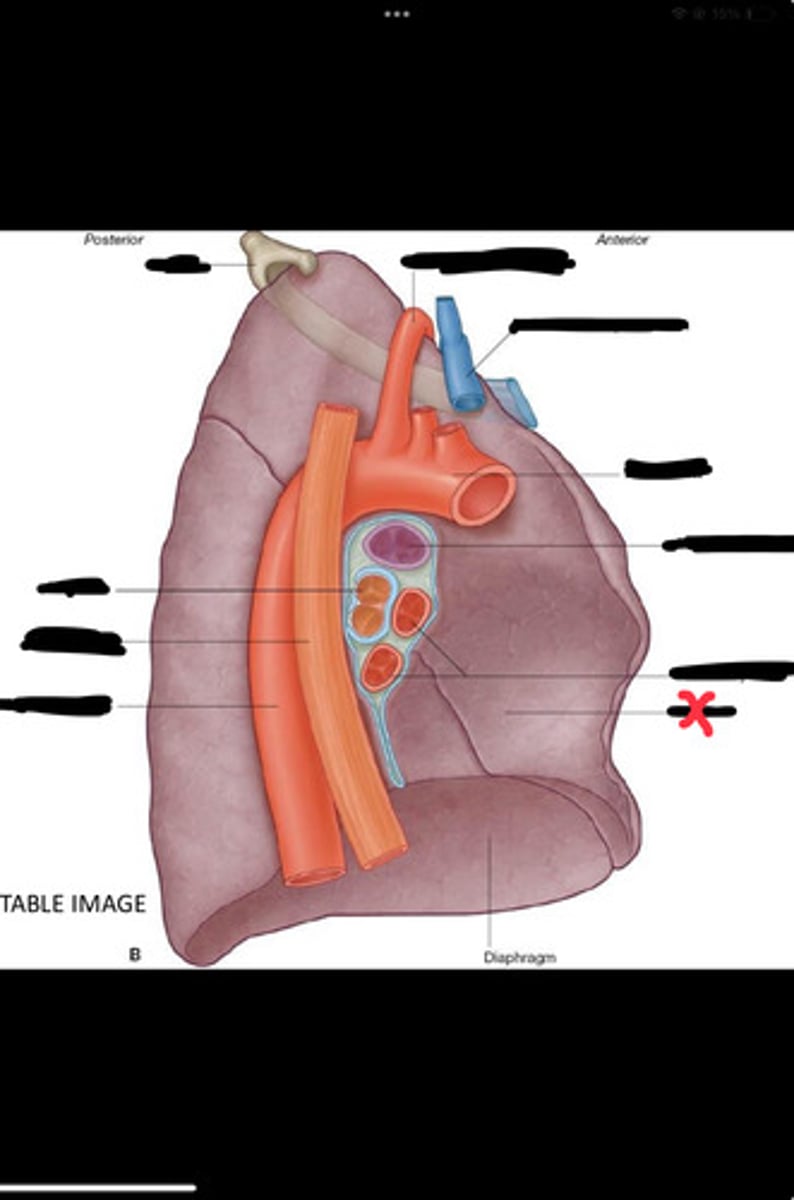

Diaphragm

Inferior vena cava

Superior vena cava

Subclavian vein

Right bracheocephalic vein

Subclavian artery

Esophagus

Bronchus

Rib 1

Left subclavian artery

Left brachiocephalic vein

Aortic arch

Pulmonary artery

Pulmonary vein

Heart

Left brachiocephalic vein

Azygos vein

Esophagus

Bronchus

Fibrous pericardium

Parietal layer of serous pericardium

Pericardial cavity

Visceral layer of serous pericardium

Junction between fibrous pericardium and adventitia

Heart

Thoracic aorta

Rib 1

Pulmonary artery

Bronchus to superior lobe